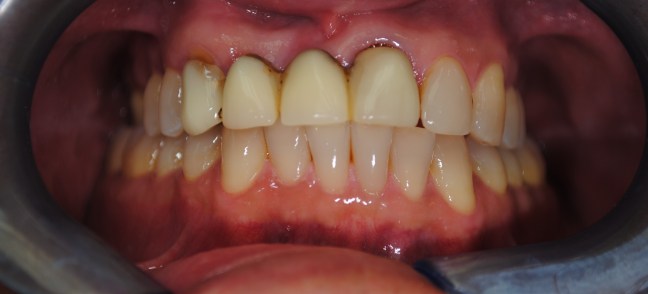

Kozmetikai kezelés: régi tömött, szuvasodott frontfogak szanálása, koronával történő leplezése, megsüllyedt harapás korrekciója.

A választott korona típusa: E-max préskerámia (fémmentes) és cirkon szóló koronák kombinációja.

A választott fogszín A1 .

A protetikai munka elkészülésének ideje: 5 munkanap.